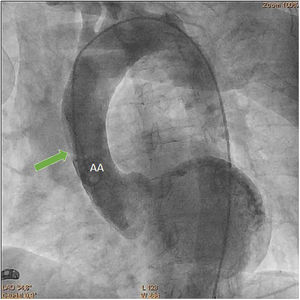

Aortography revealed a subtraction image compatible with an intimal flap in the ascending aorta (AA) (Figure 3, Clip 2), suggestive of aortic dissection (AD). The transthoracic echocardiogram revealed moderate left ventricular systolic dysfunction with anterior wall and apex hypokinesia, with no valvular changes.